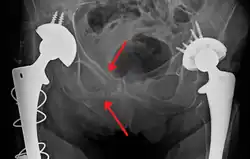

Pelvic vertical shear fracture

Fractures of the superior (in two places) and inferior pubic rami on the person's right, in a person who has had prior hip replacements